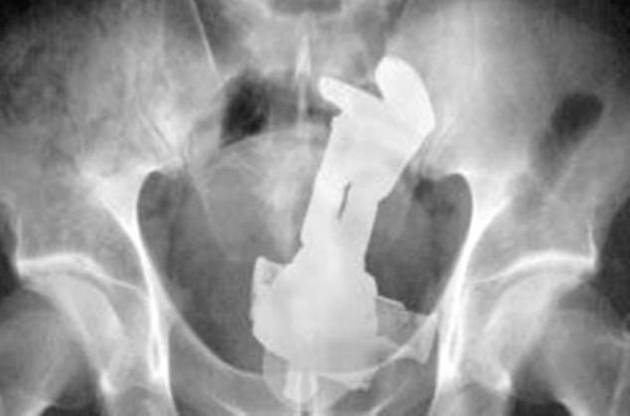

風呂場で尻餅をついたときに、17x5.5cmの哺乳瓶が偶然お尻の穴に刺さって抜けなくなってしまった男性(43)…。

おしりブツリストと、偶然災難に遭ったバズ・ライトイヤーさん、そして声に出して読みたい戒めの言葉。

「不正受給では」というコメントが見受けられますが、答えは既に出ていて、 ・「傷つけることを目的として」異物挿入した場合は故意 ・性的興味で異物挿入した結果、「意に反して」抜けなくなった場合は事故 ということになるようです。 「偶然」云々は患者の心を守るためw twitter.com/ERxICU_yakkun/…

全国健康保険協会のHP kyoukaikenpo.or.jp/g3/sb3010/r58/ によると、健康保険給付が制限される場合として画像のようなケースが挙げられています。 実際の医療現場では、患者の利益を最大限考慮した運用がなされているのだと思いますが、色んな意味で「尻餅」はしないに越したことはないですね。

某所で拾った豆知識 医者「お尻の穴に異物が入った理由は?」 患者「性的興味で……」 医「よく聞こえませんでした。故意に起こした事故には健康保険が適用されないんですよ。何故か皆さん尻餅をついたら、偶然入ったと言うんですよね。で、お尻の穴に異物が入った理由は?」 患「尻餅をつきました」